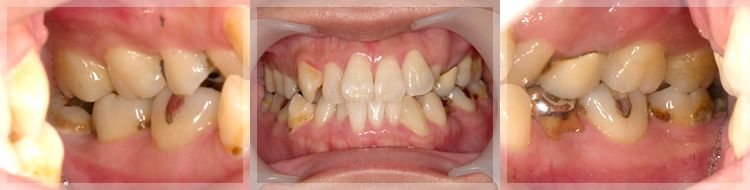

症例1. インプラントや矯正を

含めた全顎的な咬合治療

| 術前 |

年齢:36歳

主訴:歯が痛い

初診時の診断と治療方針

初診時の口腔内写真です。主訴の歯の痛みは、斜めに生え噛む面が虫歯になっている右下親知らずであることが分かります。また、その他の部位にも多くの修復物や歯列の乱配を認め、う蝕と歯周病共にリスクが高いことが考えられます。

さらに、歯列の乱配だけでなく傾斜、はまり込みを認めます。 X線写真では全顎的な軽度の歯周病の進行、左下には歯根の著しい吸収を認める乳歯も残っています。引き続き医療面接、う蝕や歯周病の詳しい検査を進め、治療方針についてカウンセリングを行った結果、患者様は顎関節の不調も感じており、インプラントや矯正を含めた全顎的な咬合治療を行っていくことになりました。